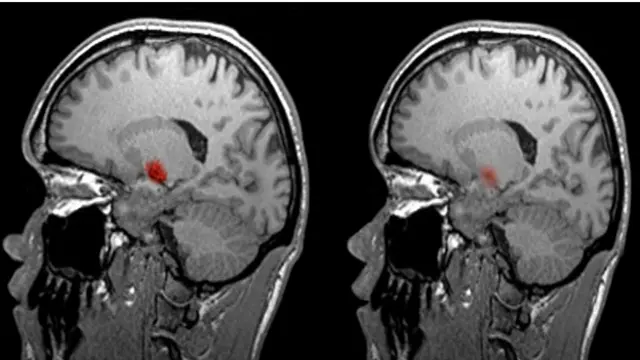

Новейшая на сегодняшний день технология сканирования головного мозга известна как функциональная магнитно-резонансная томография (фМРТ).

Я встретилась с нейробиологом Джо Девлином в Университетском колледже Лондона, где он на практике показал мне работу такого томографа.

Благодаря этой новейшей технологии нейробиологи могут следить за изменениями насыщенности мозга кислородом.

Автор фото, SPL

Области мозга, занятые решением определенных задач - например, лингвистических - расходуют больше энергии, поэтому и циркуляция крови в них будет повышенной. Томограф как раз и отслеживает приток крови к определенным участкам мозга.

"На экране можно видеть, что участки мозга, отвечающие за выполнение текущего задания, интенсивно светятся", - говорит Девлин.

Так, при необходимости подбирать слова при разговоре активируются одни области мозга, а при простом счете - монотонной задаче, характеризующейся низкой мыслительной активностью - другие.

Хотя данная технология и дает ученым представление о том, какие области мозга задействованы в выполнении той или иной задачи, томограф, разумеется, не способен читать человеческие мысли.

Тем не менее, эти аппараты революционизировали изучение головного мозга. "Раньше мы имели дело с пациентами, перенесшими мозговые травмы - мы могли определить область повреждения и скореллировать эту информацию с наблюдениями за тем, как изменилось поведение больного", - говорит Девлин.

Теперь магнитно-резонансная томография дает исследователям возможность заглянуть внутрь здорового мозга и понаблюдать за тем, каким образом задействуются разные его отделы и как они взаимосвязаны друг с другом.